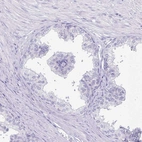

Immunohistochemistry analysis in human cerebral cortex and liver tissues using HPA038296 antibody. Corresponding ERMN RNA-seq data are presented for the same tissues.